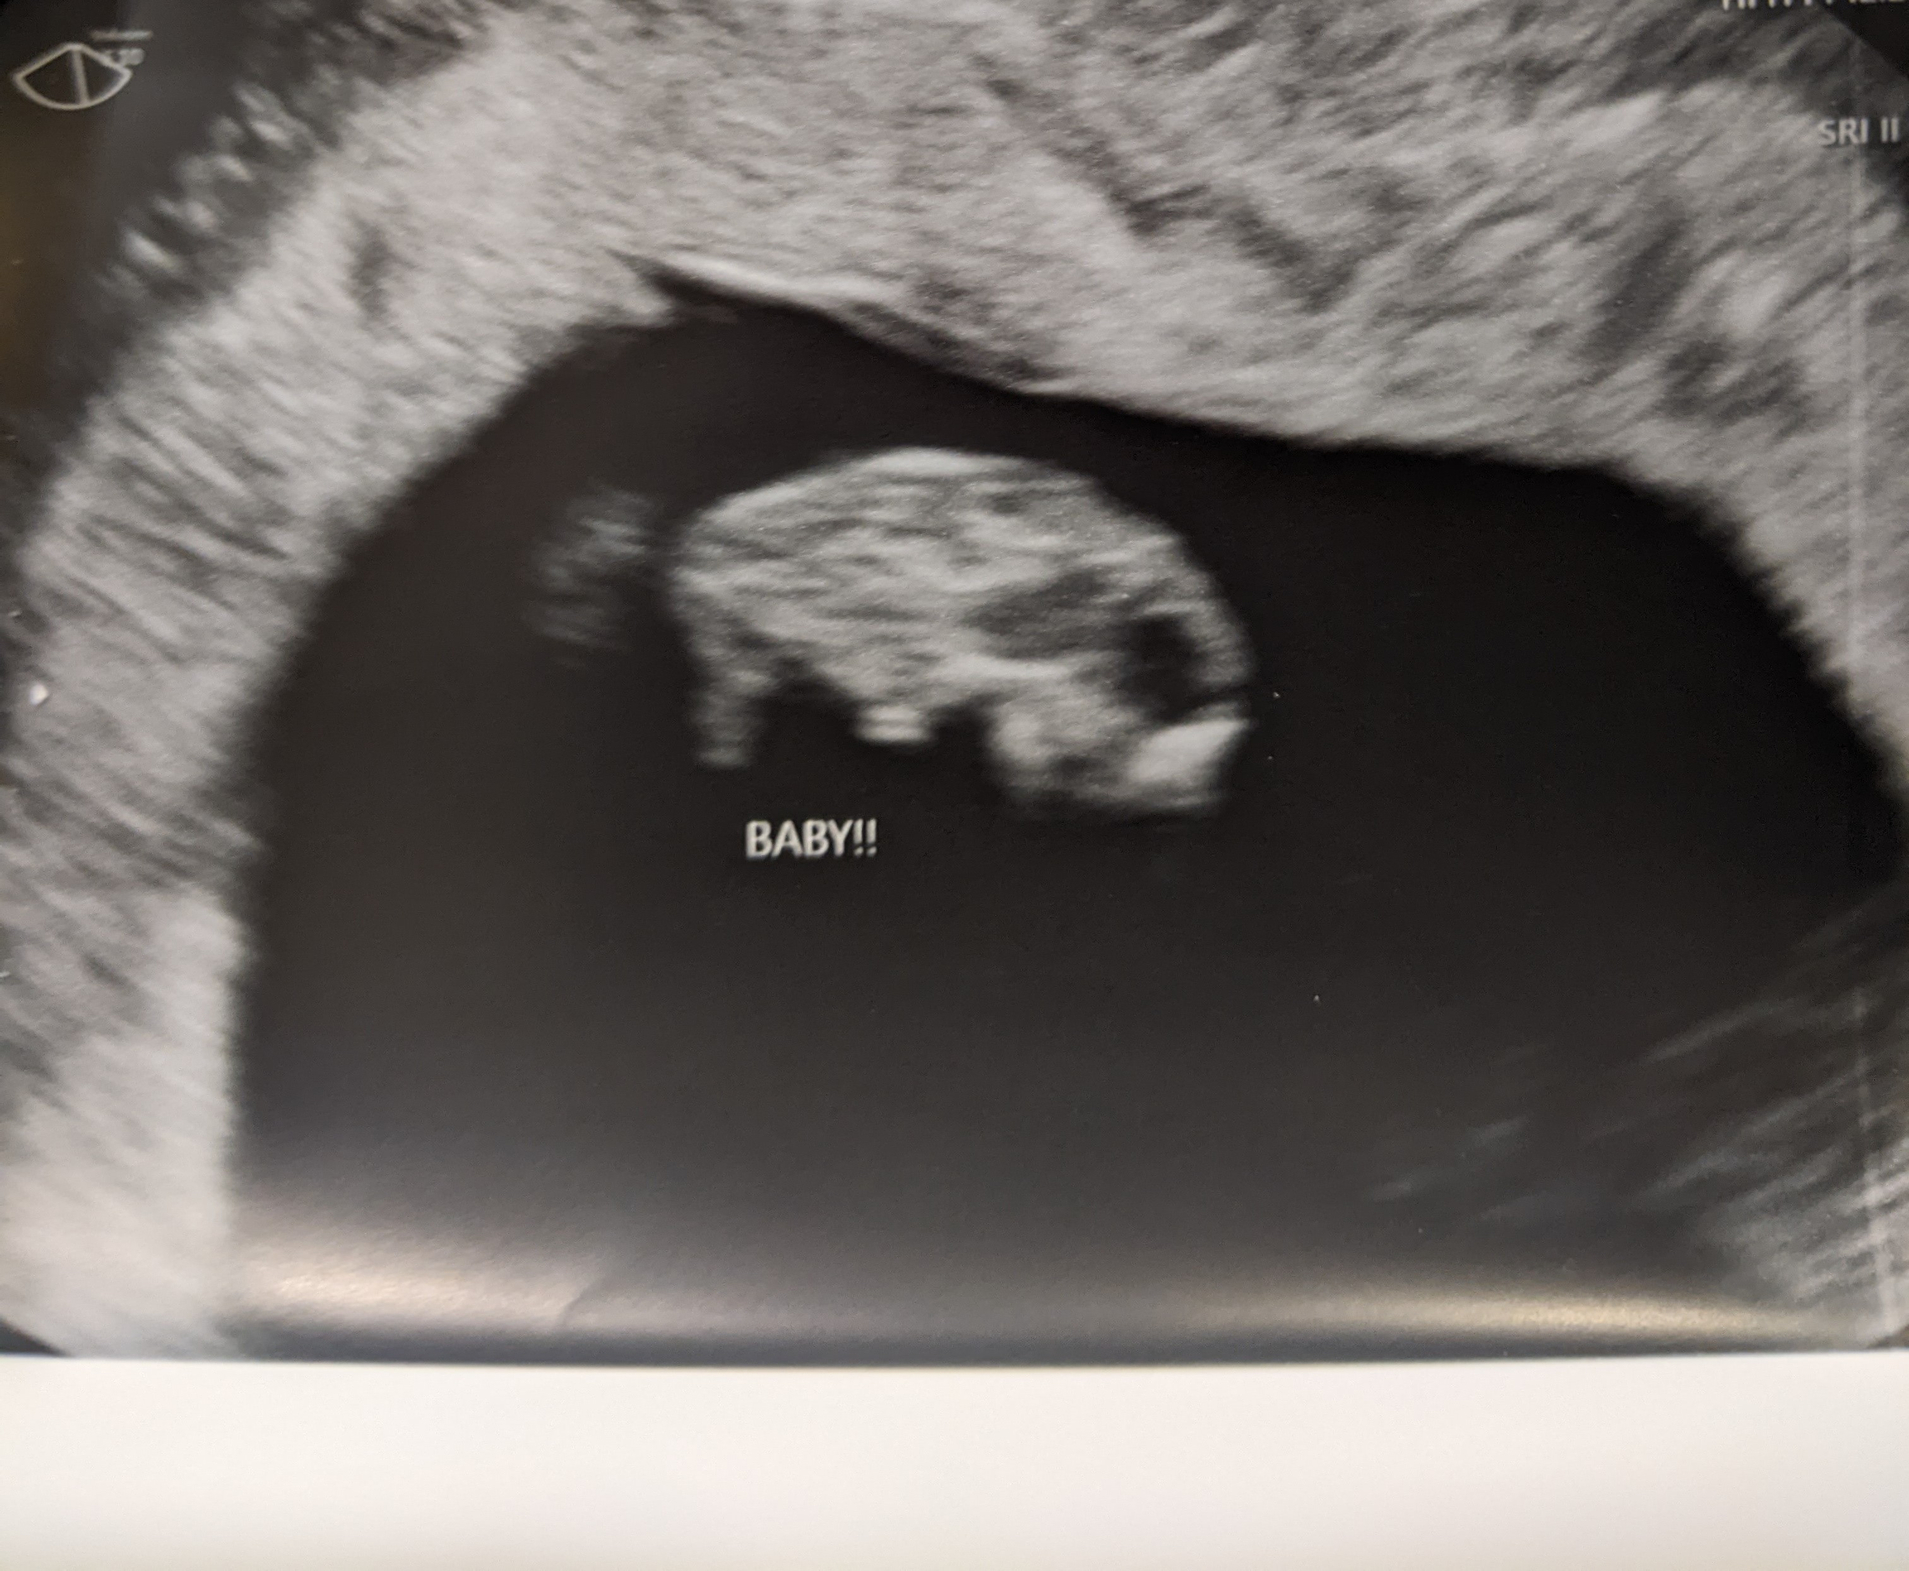

Had an elective ultrasound because I couldn't get into OB u til 10 weeks BUUUUT baby had a beautiful little heartbeat of 162 and the cutest little arm and leg buds. For an abdominal ultrasound, I was happy to see pretty decent detail 💙

Baby is 10w6d today! I’m a week ahead and a week closer from getting away from this damn morning sickness!!

Little peanut’s heartbeat is 165. I edited the photo to describe it. Look at that chunky belly!! And yes I cried too! My partner looked like a deer in headlights happy.